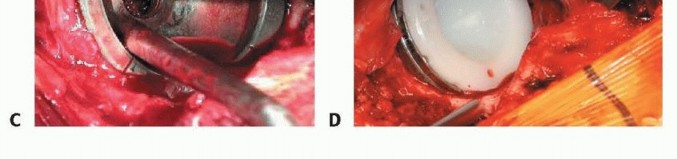

الشكل التوضيحي 3: زرع المكون الحقّي. أ. يتم استخدام المجوّف النهائي لتقييم وضع المكون، وتغطية العظم، والتثبيت. ب. يتم زرع المكون الحقّي. ج. يستخدم الثقب المركزي للتحقق من أن الكأس مثبت بالكامل. د. يتم إدخال البطانة الفعلية في الكأس.

يجب أن يكون الزرعة الفعلية أكبر بمقدار 1 إلى 2 ملم من المجوّف الأخير. يجب أن يعرف الجراح القطر الفعلي للزرعة، مع الأخذ في الاعتبار أي حافة أو طلاء. الزرعات التي تكون أكبر من حجم المجوّف الأخير بمقدار 4 ملم أو أكثر ترتبط بخطر الكسر. ثم يتم زرع المكون الحقّي، مع الحرص على توسيط الزرعة. يجب أن يكون الجانب السفلي الإنسي للكأس عند مستوى علامة الدمعة بزاوية 35 إلى 45 درجة من التبعيد و10 إلى 20 درجة من التدوير الأمامي. ثم يتم إدخال البطانة التجريبية أو البطانة الفعلية.